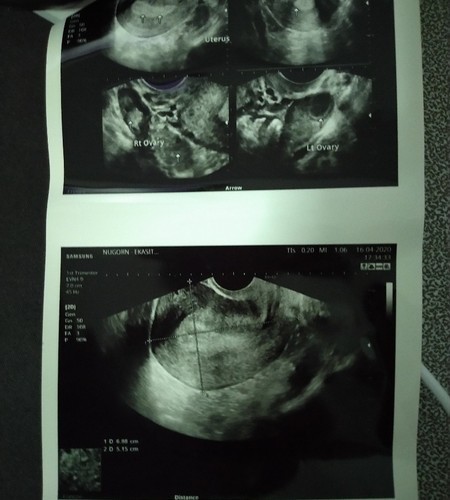

ประจำเดือนครั้งสุดท้ายมาวันที่ 9-13 มีนาคม ตรวจที่ตรวจครรภ์แบบ first response ขึ้นว่าตั้งครรภ์ และตรวจกับที่ตรวจครรภ์แบบหยด เจอ 2 ขีดจางๆ วันนี้ 16 เมษายน ไปหาหมอ เพื่อตรวจยืนยัน หมออัลต้าซาวผ่านช่องคลอด ยังไม่เจอถุงตั้งครรภ์ เห็นแต่ผนังมดลูกที่หนาขึ้น หมอเลยนัดอีกที 30เมษา แบบนี้ตกลงว่าท้องไหมคะ มีแม่ๆคนไหนพอจะมีข้อมูล หรือประสบการณ์ ขอปรึกษาหน่อยค่ะ